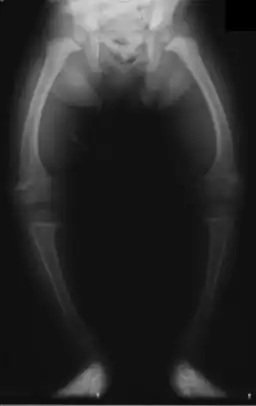

X-ray of the legs in a two-year-old child with rickets

The X-ray, or radiograph, in the article is the classic image of advanced rickets sufferers: bow legs (outward curve of long bone of the legs) and a deformed chest. Changes in the skull also occur causing a distinctive "square headed" appearance. These deformities persist into adult life.